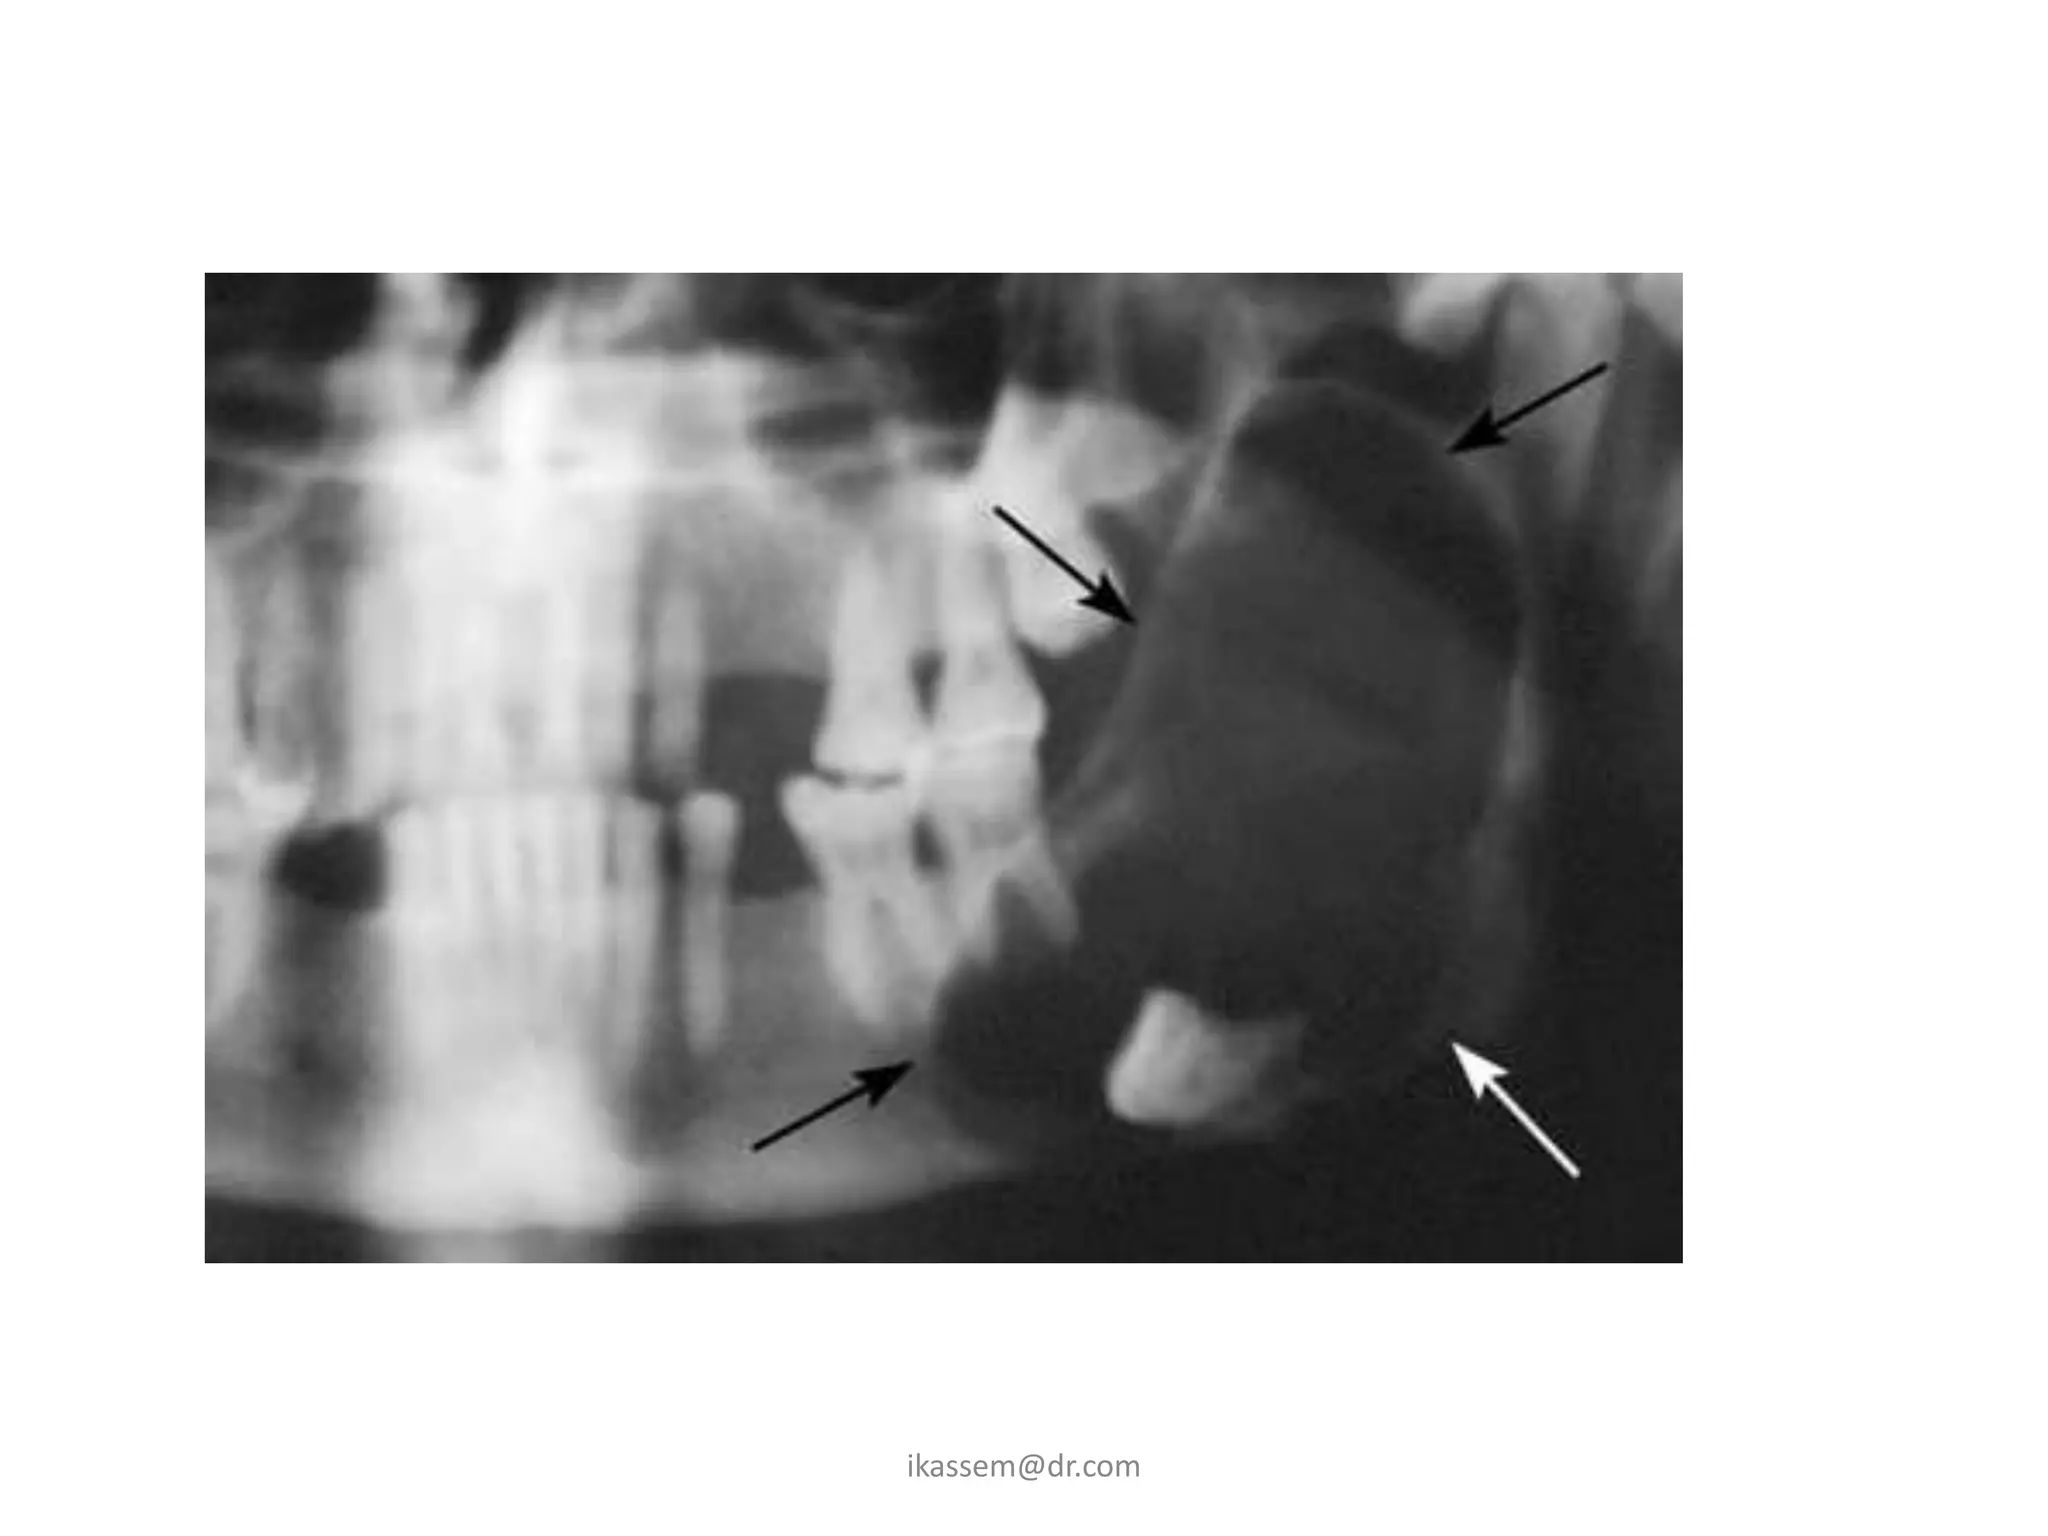

F. Odontogenic cyst and Tumors

• The dental follicle may

undergo cystic

degeneration and

become a dentigerios

cyst or keratocyst.

• A meloblastoma may

developed from

epithelium within the

dental follicle

G. Fracture of the jaw

• impacted third molar

occupies space that is

usually filled with bone,

this weaken the

mandible and render

the mandible to

fracture.